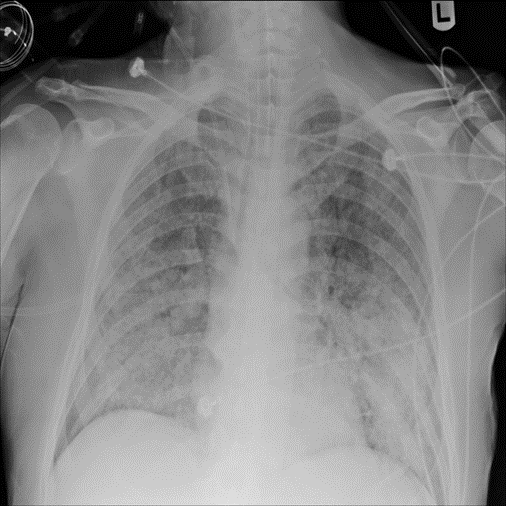

Figure 9: Typical CXRs with pneumonia-like lung opacity from among the top 1,000 CXRs most likely to have an abnormality according to the logarithm posterior probability out of the 13,863 abnormal CXRs. The lesion is indicated with a red arrow if applicable.

Figure 9 shows CXRs suggested to have pneumonia-like lung opacity with the logarithm posterior probability. These CXRs are the top 1,000 CXRs most likely to have an abnormality out of the 13,863 abnormal CXRs.